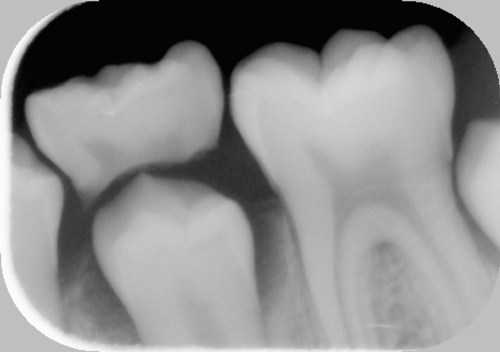

I kæben under mælketænderne ligger de nye blivende tænder, som er under udvikling. Mælketændernes rødder bliver opløst, efterhånden som de nye tænder vokser. Til sidst falder mælketanden ud, når hele tandens rod er væk.

På første røntgenbillede er den blivende tand ved at skubbe mælketanden ud. På det andet er mælketanden lige ved at falde ud.

Normalt ligger de nye tænder lige nedenunder mælketænderne, som ses på første billede. På andet billede mangler anlæg til den blivende tand.